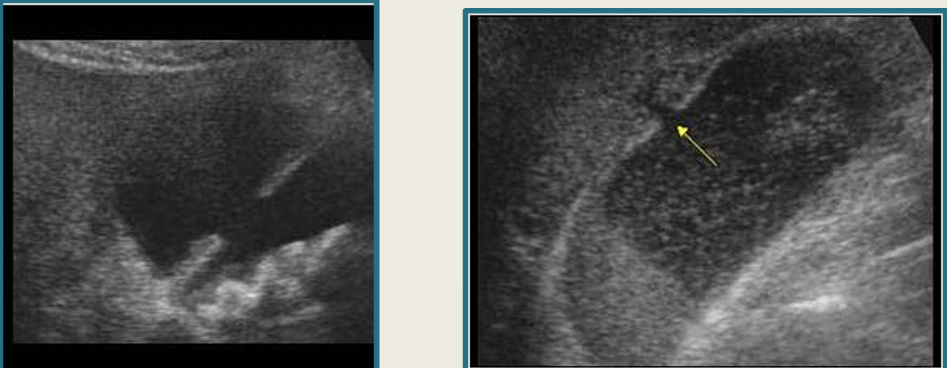

term image

sludge

porcelain GB